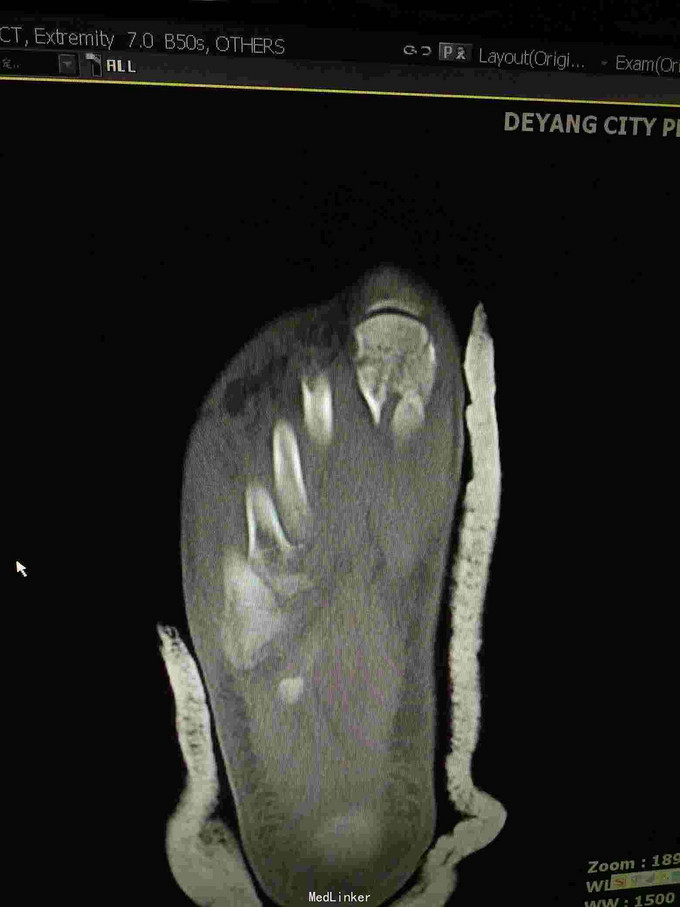

主诉:重物砸伤致右足疼痛伴活动受限2小时; 病史:患者不慎被重物砸伤右足,即感疼痛,活动受限,不能行走,不办皮肤破溃及活动性出血。

查体:右足畸形肿胀,足背少许擦挫伤,无开放性伤口,明显压痛,右足远远端感觉及血运可。 x片:右足第1、2跖骨基底部骨折,第3跖骨基底部可疑骨折; ct:右足第1~4跖骨骨折。

诊断:右足第1、2跖骨粉碎性骨折;右足lisfrance损伤; 治疗:石膏固定,消肿止痛,行右足跖骨骨折切开复位内固定,第1跖骨钢钉及克氏针固定,第2跖骨钢板固定。